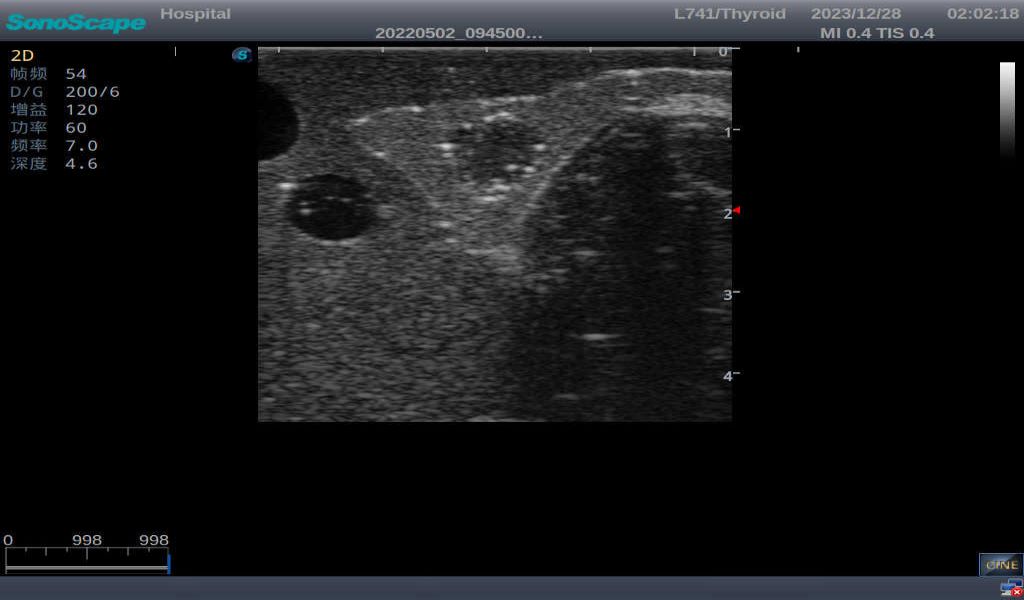

3)       It comes with four (4) thyroid modules and can show five (5) ultrasonic images: normal thyroid, thyroid adenoma, thyroid cancer, nodular goiter, thyroid cyst

Thyroid cyst, which fluid area, dark and echo-free area can be seen